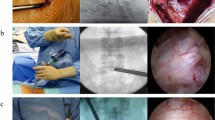

Decompression Procedure: Under endoscopic guidance, the K-wire was identified (Fig. 2), clarifying the lamina boundaries to prevent disorientation. The hypertrophic ligamentum flavum and abnormal fatty hyperplasia were removed to expose the dural edge and ipsilateral traversing nerve root. Protruded disc fragments were extracted using pituitary forceps and Kerrison punches. After removal, nerve root mobility was assessed with a hook dissector.

Closure: Annulus fibrosis repair was performed in all patients (Fig. 3). Wounds were closed using 3 − 0 absorbable sutures and skin adhesives.